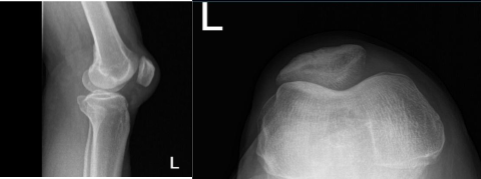

He was physically examined and an MRI was performed, which showed a complete tear of the quadriceps along with lateral meniscus tear, and partial tear of the ACL. The patient came to the emergency room due to intractable pain. We discussed treatment options and the patient opted for surgical management.

The patient underwent arthroscopic surgery. The procedures conducted were partial lateral meniscectomy, chondroplasty, ACL debridement and open repair of the quadriceps of the left knee. A left lateral entry portal was made and the scope was entered.

The scope was moved to the patellofemoral joint where trochlea grade 2 to grade 3 chondral damage was found. The chondral damage was debrided from the medial portal and followed by the lateral portal.

Copious lavage was performed. Arthroscopic pictures were taken and saved. The scope was removed. The knee was extended. The table was extended and a proper draping was performed. A midline vertical incision was put and centered over the superior pole of the patella.